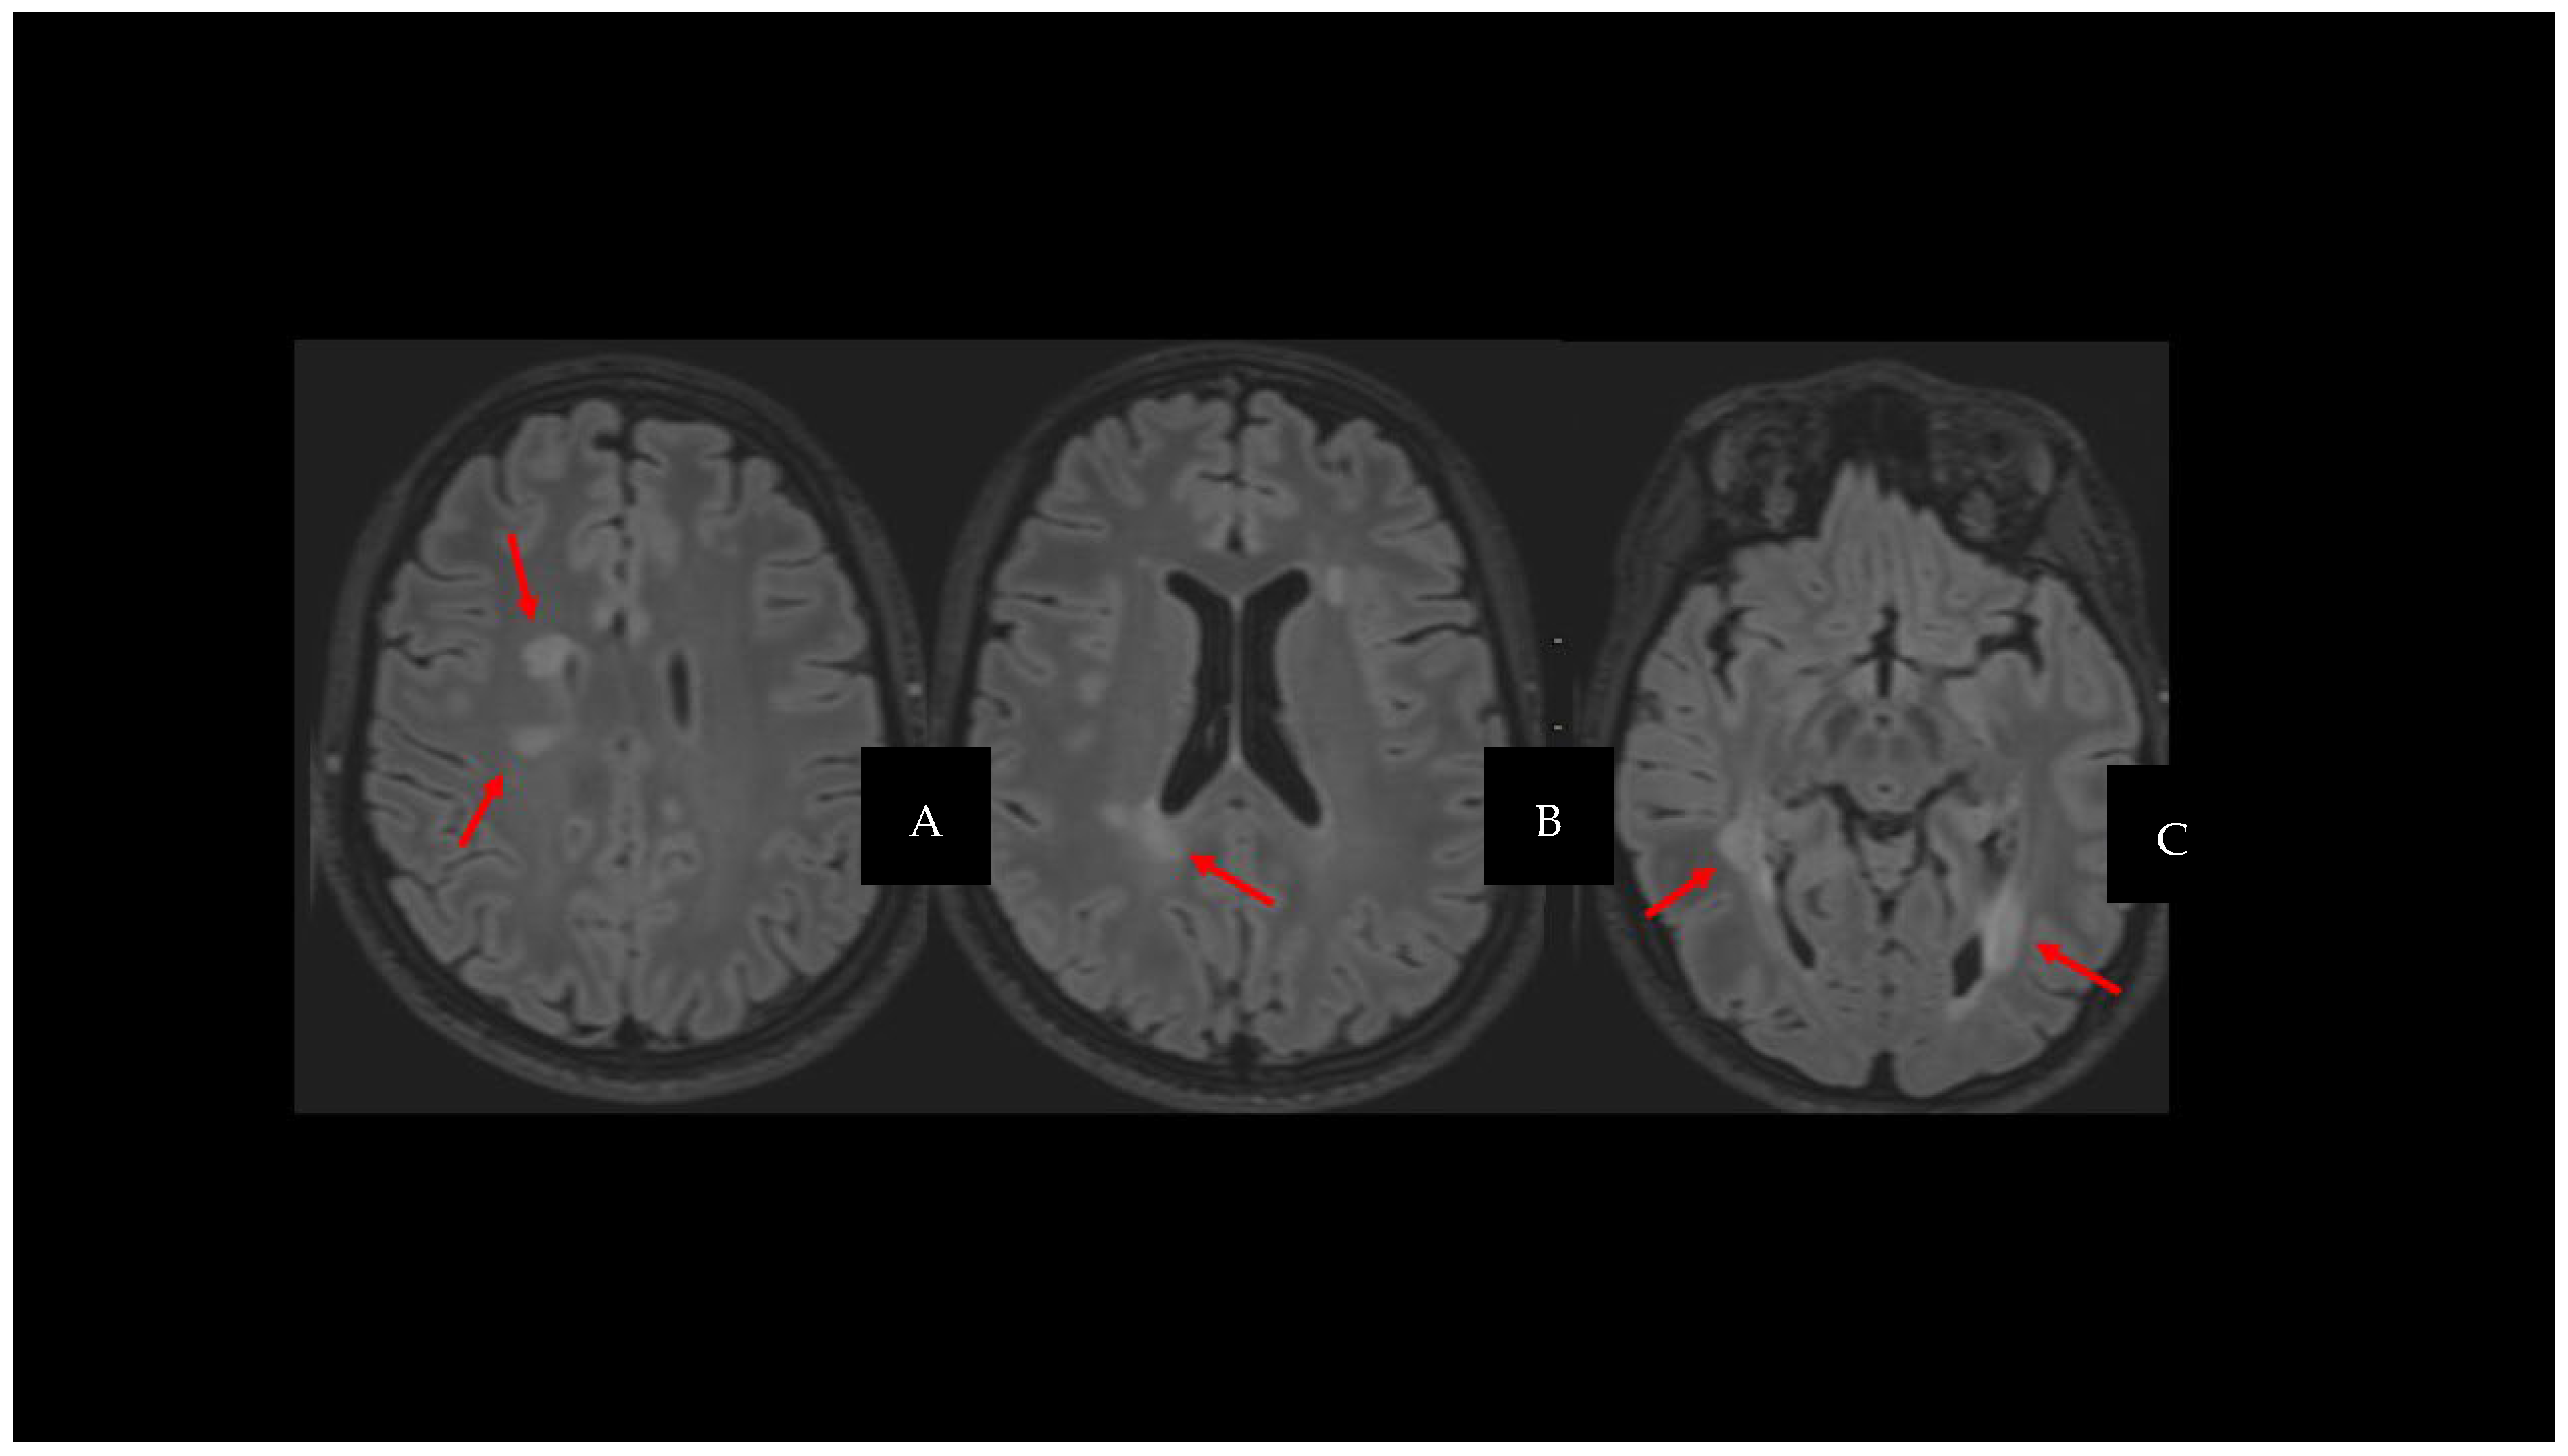

3.1. Central Vein Sign

3.2. Paramagnetic Rim Lesions